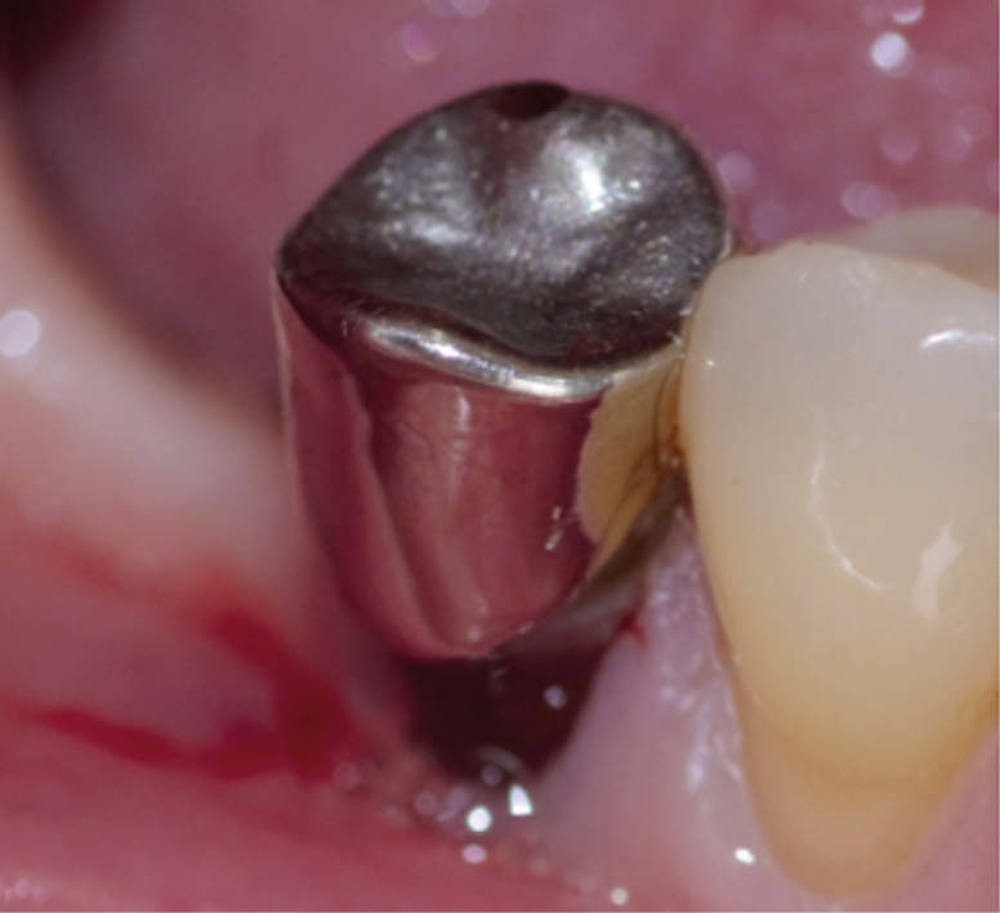

Une patiente de 53 ans, sans antécédent médico-chirurgical, consulte pour une gêne en lien avec une couronne métallique inadaptée sur la 45, réalisée une vingtaine d’années auparavant. L’examen clinique révèle un joint non étanche en vestibulaire associé à une lésion cervicale d’usure, nécessitant une réintervention et un retraitement endodontique. À la dépose de la couronne, la dent présente une reconstitution coronaire en amalgame ; aucune surface amélaire n’est présente et la prémolaire ne compte que deux parois avec une hauteur supérieure à 2 mm (fig. 1).